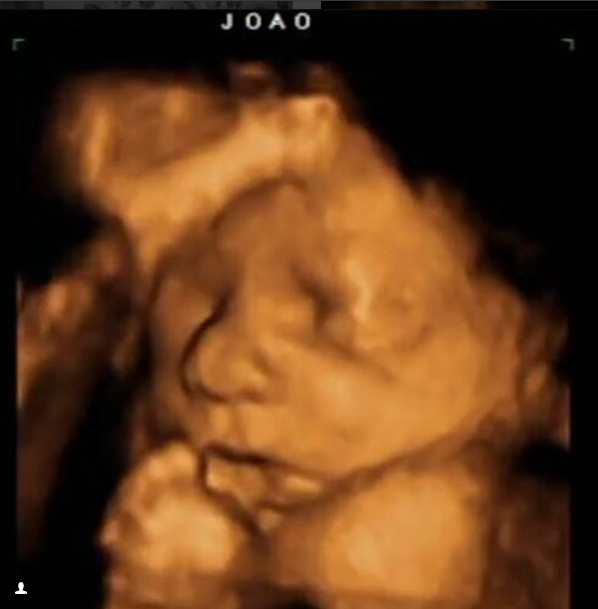

A primeira delas é bem conhecida por nós. Ex-editora de arte da TOPVIEW, a designer e arquiteta Iraisi Gehring foi, por uma década, responsável pelo projeto gráfico e artístico da revista impressa. Ela e o marido, Eduardo Gimenes Peres, esperam João, de 32 semanas – primeiro filho do casal.